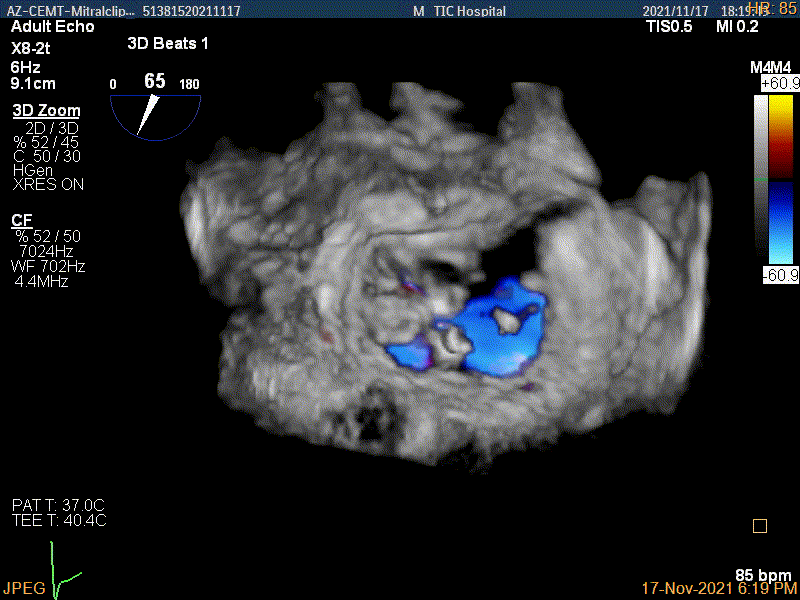

3D-color MV view:源自于交界区的大量反流

3Dcolor证实残余分流主要来源于残余脱垂

3D-color视图下两个夹子间少量残余反流